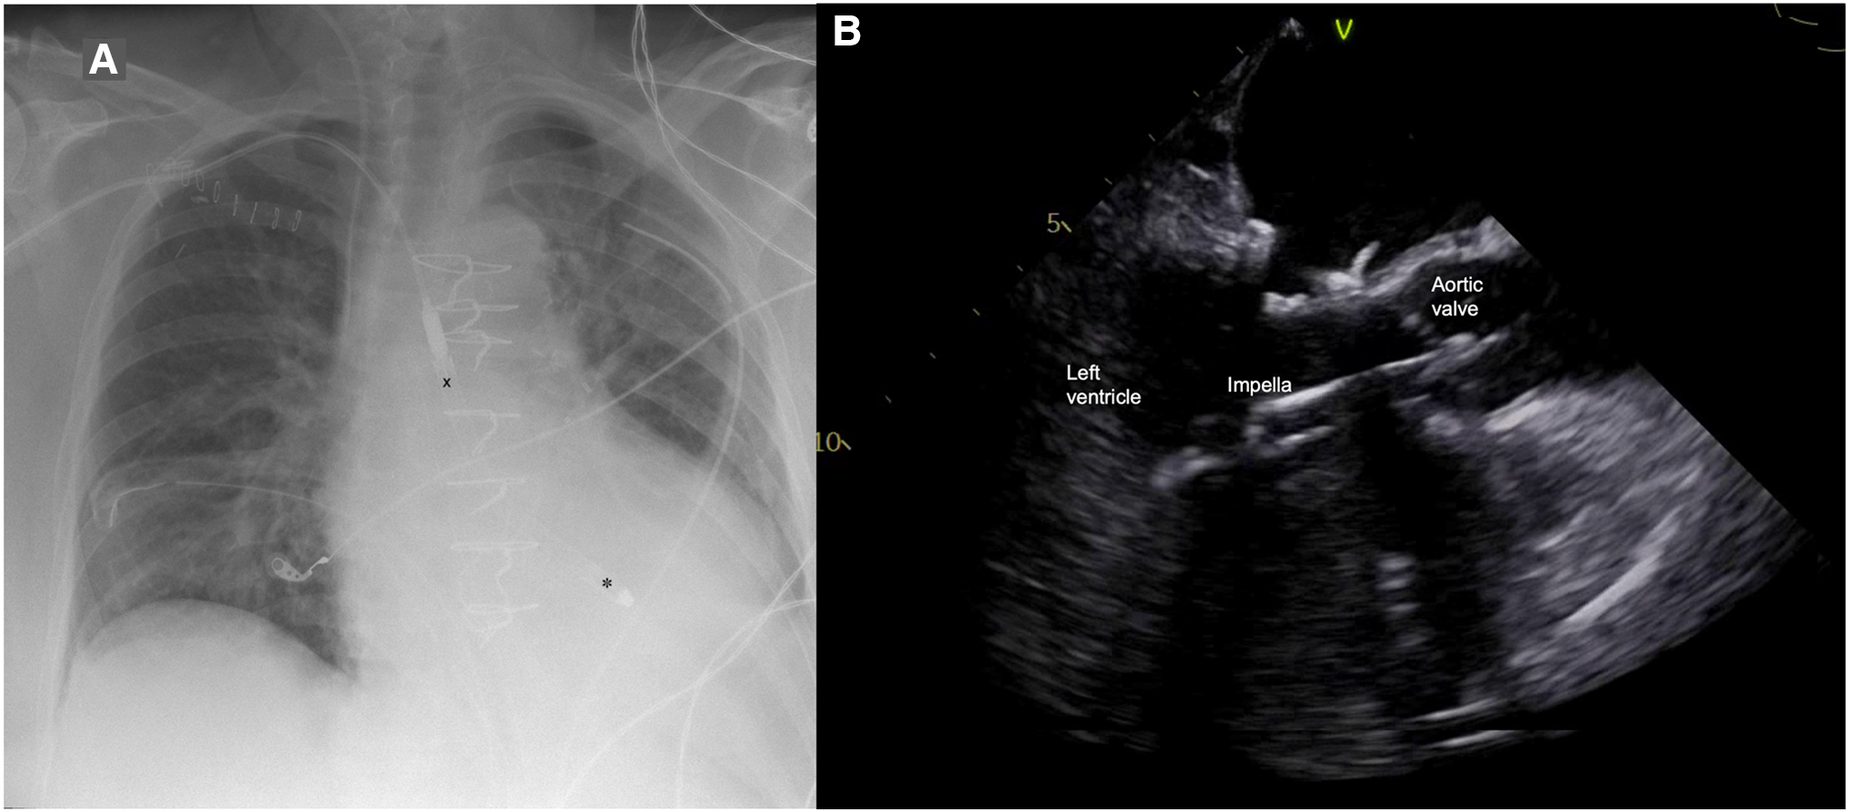

Figure 1

(A) Postoperative chest x-ray with Impella 5.5 pump (X outflow, ✽ inflow); (B) Impella position in transesophageal echocardiography.